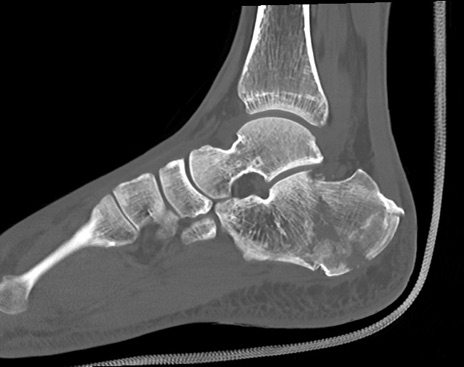

症例37 左足関節CT(矢状断像)

左足関節CT